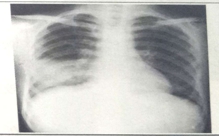

試題1:男性,26歲,受涼后寒顫高熱,咳嗽,咳鐵銹色痰5天(2分)

A.肺癌

B.氣胸

C.正常胸片

D.肺炎

E.胸腔積液

答案:D